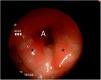

Recién nacido a término con rasgos dismórficos, ventriculomegalia bilateral y comunicación interventricular e interauricular que precisa ingreso por distrés respiratorio que requiere soporte respiratorio con ventilación mandatoria intermitente a 30rpm. Presenta episodios de tos y atragantamiento en todas las tomas. Ante la sospecha de fístula traqueoesofágica, se indica una exploración de la vía aérea mediante lente rígida de 3mm en respiración espontánea. Se observa hendidura laringotraqueoesofágica tipo III (figs. 1 y 2). Se realiza laringotraqueoplastia por abordaje abierto. En el control endoscópico a los 16 meses se observa una hendidura grado 1 que precisa de nueva cirugía. En el último control, no se observan hendiduras, con normoposición de epiglotis y aritenoides unidos por la comisura posterior (fig. 3).

La hendidura laringotraqueoesofágica se caracteriza por un defecto en la pared posterior de la laringe que puede extenderse hasta la tráquea1. Puede asociar alteraciones cardíacas, urogenitales y craneofaciales1–3. En función de su extensión, existen cuatro subtipos. Las hendiduras laringotraqueoesofágicas tipo I pueden ser manejadas de manera conservadora. Se ha descrito la corrección endoscópica del grado I y II3. Los grados III y IV precisan de cirugía abierta por la extensión del defecto1–3. El diagnóstico requiere una alta sospecha en un neonato con dificultad respiratoria, tos y atragantamiento durante las tomas. La exploración de la vía aérea permite un diagnóstico certero. Además, es útil en el seguimiento para demostrar otras alteraciones como la laringomalacia y la traqueomalacia, así como estenosis subglótica o fístulas traqueoesofágicas.